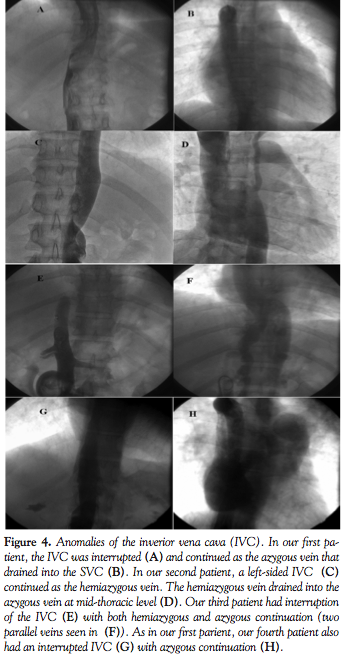

PTMC is an established method of treatment for rheumatic mitral stenosis with morphologically suitable mitral valves.1,6 However, the traditional transfemoral approach to transseptal puncture is not possible in the presence of an interrupted IVC. Our first and fourth cases had interruption of IVC with azygous continuation, while our second case had a left-sided interrupted IVC and hemiazygous continuation. In our third case, the interrupted IVC was drained by both the azygous and the hemiazygous systems (Figure 4).

The treatment options available when rheumatic mitral stenosis co-exists with interrupted IVC include: retrograde transaortic approach to the mitral valve, percutaneous transhepatic mitral commissurotomy, transjugular approach to septal puncture, or surgical open mitral valvotomy/mitral valve replacement. In the retrograde approach, a special ‘steering’ catheter is used to guide the guidewire and balloon across the aortic and mitral valve.7 Since the entire system has to be delivered via the femoral artery, the risk of injury to the femoral artery increases. Moreover, the passage of balloon through the cordae tendinae can result in chordal rupture and severe mitral regurgitation.7 The transhepatic approach has been described in 1 patient with rheumatic mitral stenosis with an IVC Greenfield filter. However, in view of the risk of liver injury and lack of expertise with transhepatic catheterization, this approach was not considered. The transjugular approach was first described in patients with rheumatic mitral stenosis and anatomical LA distortion as an alternative to the femoral approach.8 Septal puncture was done using the traditional Brokenborough needle in the 45° right anterior oblique (RAO), 2 cm below the upper border of the opacified LA. PTMC was completed using traditional PTMC hardware and Inoue balloon. The authors noted that the adult Brokenborough needle was too long and unwieldy for transjugular PTMC and opined that a shorter needle would make transseptal puncture easier through the jugular approach. In a second paper, the same group reported successful jugular PTMC in 10 patients with anatomical abnormalities, including 1 patient with IVC anomaly. Endry’s pediatric transseptal puncture needle (Cook Cardiology) was used with considerable ease in these patients.9 Compared to the Brokenborough needle (71 cm in length), the Endry’s needle is shorter (30 cm in length) and offers easy maneuverability from the upper limb. In addition, subsequent steps in PTMC were also modified, namely the positioning of a 20 cm, 14 Fr Cook sheath directly into the LA, a balloon floatation catheter to assist LV entry, and the use of the Jomiva balloon for mitral valve dilatation. In the present series, we used a pediatric Brokenborough needle (51 cm in length) for septal puncture and conventional hardware to perform the remaining steps of PTMC. Earlier, Sullebarger et al also reported the successful use of a pediatric Brokenborough needle and conventional hardware to perform transjugular PTMC in 1 patient with rheumatic mitral stenosis complicated by prior liver transplantation and severe IVC distrortion.10 The pediatric Brokenborough offers better maneuverability when compared to the adult needle and is also easily available. The needle tip is manually bent to create a more acute angle which favors septal puncture and prevents the needle from slipping down along the septum. The LA opacification seen in the levophase of the PA angiogram acts as a roadmap. The septum is punctured along the opacified border of the LA in the LAO view midway between the pigtail catheter (placed in the non-coronary sinus) and the vertebral border, a little below the level of the pigtail. In case of a lower septal puncture (as in case 1), we use an ‘over-the-wire’ approach wherein the 0.025˝ wire is directly placed inside the LV instead of the LA. The balloon is then easily guided over the wire into the LV across the mitral valve. This over-the-wire balloon entry into the LV has been used extensively at our institute in femoral PTMCs with difficulty in entering the LV.11 The procedure is safe and the occurrence of LV perforation is extremely rare. Appropriately sized Acura balloons were used for dilatation with successful commissural splitting in all 4 cases. The Accura balloon is similar to the Inoue balloon except that it doesn’t have a vent port. It has been shown to be as effective and safe as the Inoue balloon, while being more economical.12